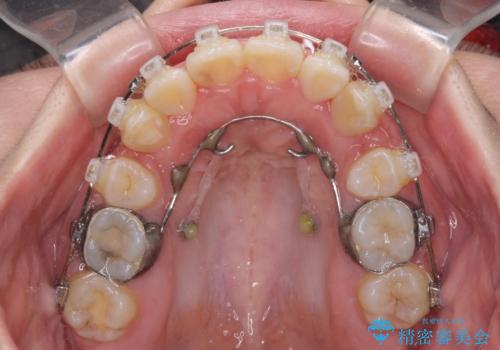

- 矯正装置

- クリアブラケット

- 上下の八重歯やデコボコを気にして来院された患者様です。

上下ともに八重歯が顕著であったので、上下左右第一小臼歯4本を抜歯し、補助装置を使用して速やかに改善しながら、ワイヤー装置にて矯正治療を行うこととしました。

気になっていた八重歯は装置装着から3か月ほどで解消されました。

2年以内を目標として治療を開始しましたが、1年半ほどで終えることができました。